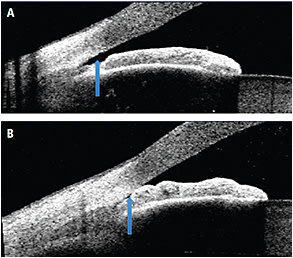

Non-contact AS-OCT visualizes spatial relationships within the anterior segment and objectively measures the ACA. In addition, the infrared laser combined with the real-time eye position monitor permits the precise capture of angle morphology in the dark. Darkroom conditions are imperative in angle imaging to increase the detection of angle closure (Figure 1).

Figure 1: Anterior chamber angle imaged with AS-OCT. Block arrows show an open angle in lighted conditions (A) and closure of the angle in darkness (B).